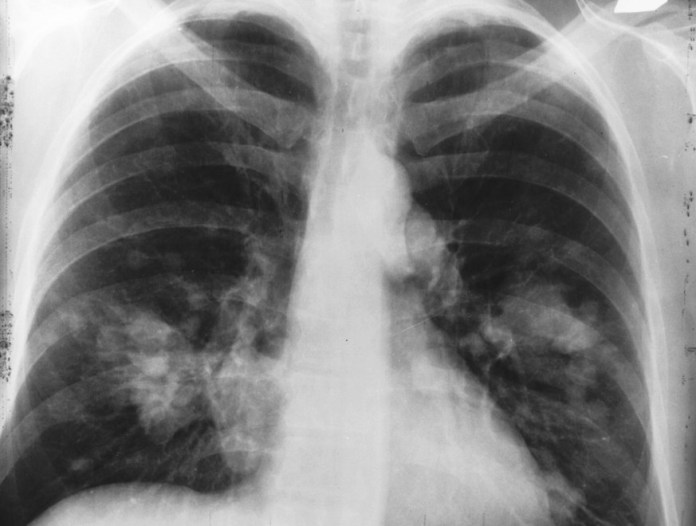

A paper that was recently published on the Arviv.org dubbed Single-Shot Single-Scale Lung Nodule Detection shows a deep learning technique for lung detection.

Through a convolutional neural network, researchers based at the University of Florida-based Center for Research in Computer Vision were in a position to spot small nodules of lung cancer with about 95- 97% accuracy.

The system used by the researchers, S4ND, separated input data into a grid of cells before performing classification for all cells at the same time. About 36 of its convolution layers (consisting five “densely connected” blocks made up of six layers) considered information drawn from the whole scan in a bid to project the existence of nodules in a given cell.

The researchers conducted their training of S4ND on one Nvidia Titan XP GPU workstation featuring 64 GB of RAM. The fed it with 888 CT scans derived from the Luna dataset, which is a public dataset of CT lung cancer scans that have been interpreted by human radiologists.

The scans had been sampled to allow them to appear in random areas in a bid to avoid any case of bias. To test the accuracy of the system, the researchers involved fed the scans into it again. However, the second time, they moved in four different directions by 32 pixels.

The S4ND proved to be better in dealing with the variation in position, shapes, and textures of nodules compared to traditional computer-backed detection systems. Also, the researchers revealed that the system had an easier time in reconciling all the discrepancies existing between huge search spaces and the relatively small nodes as well.